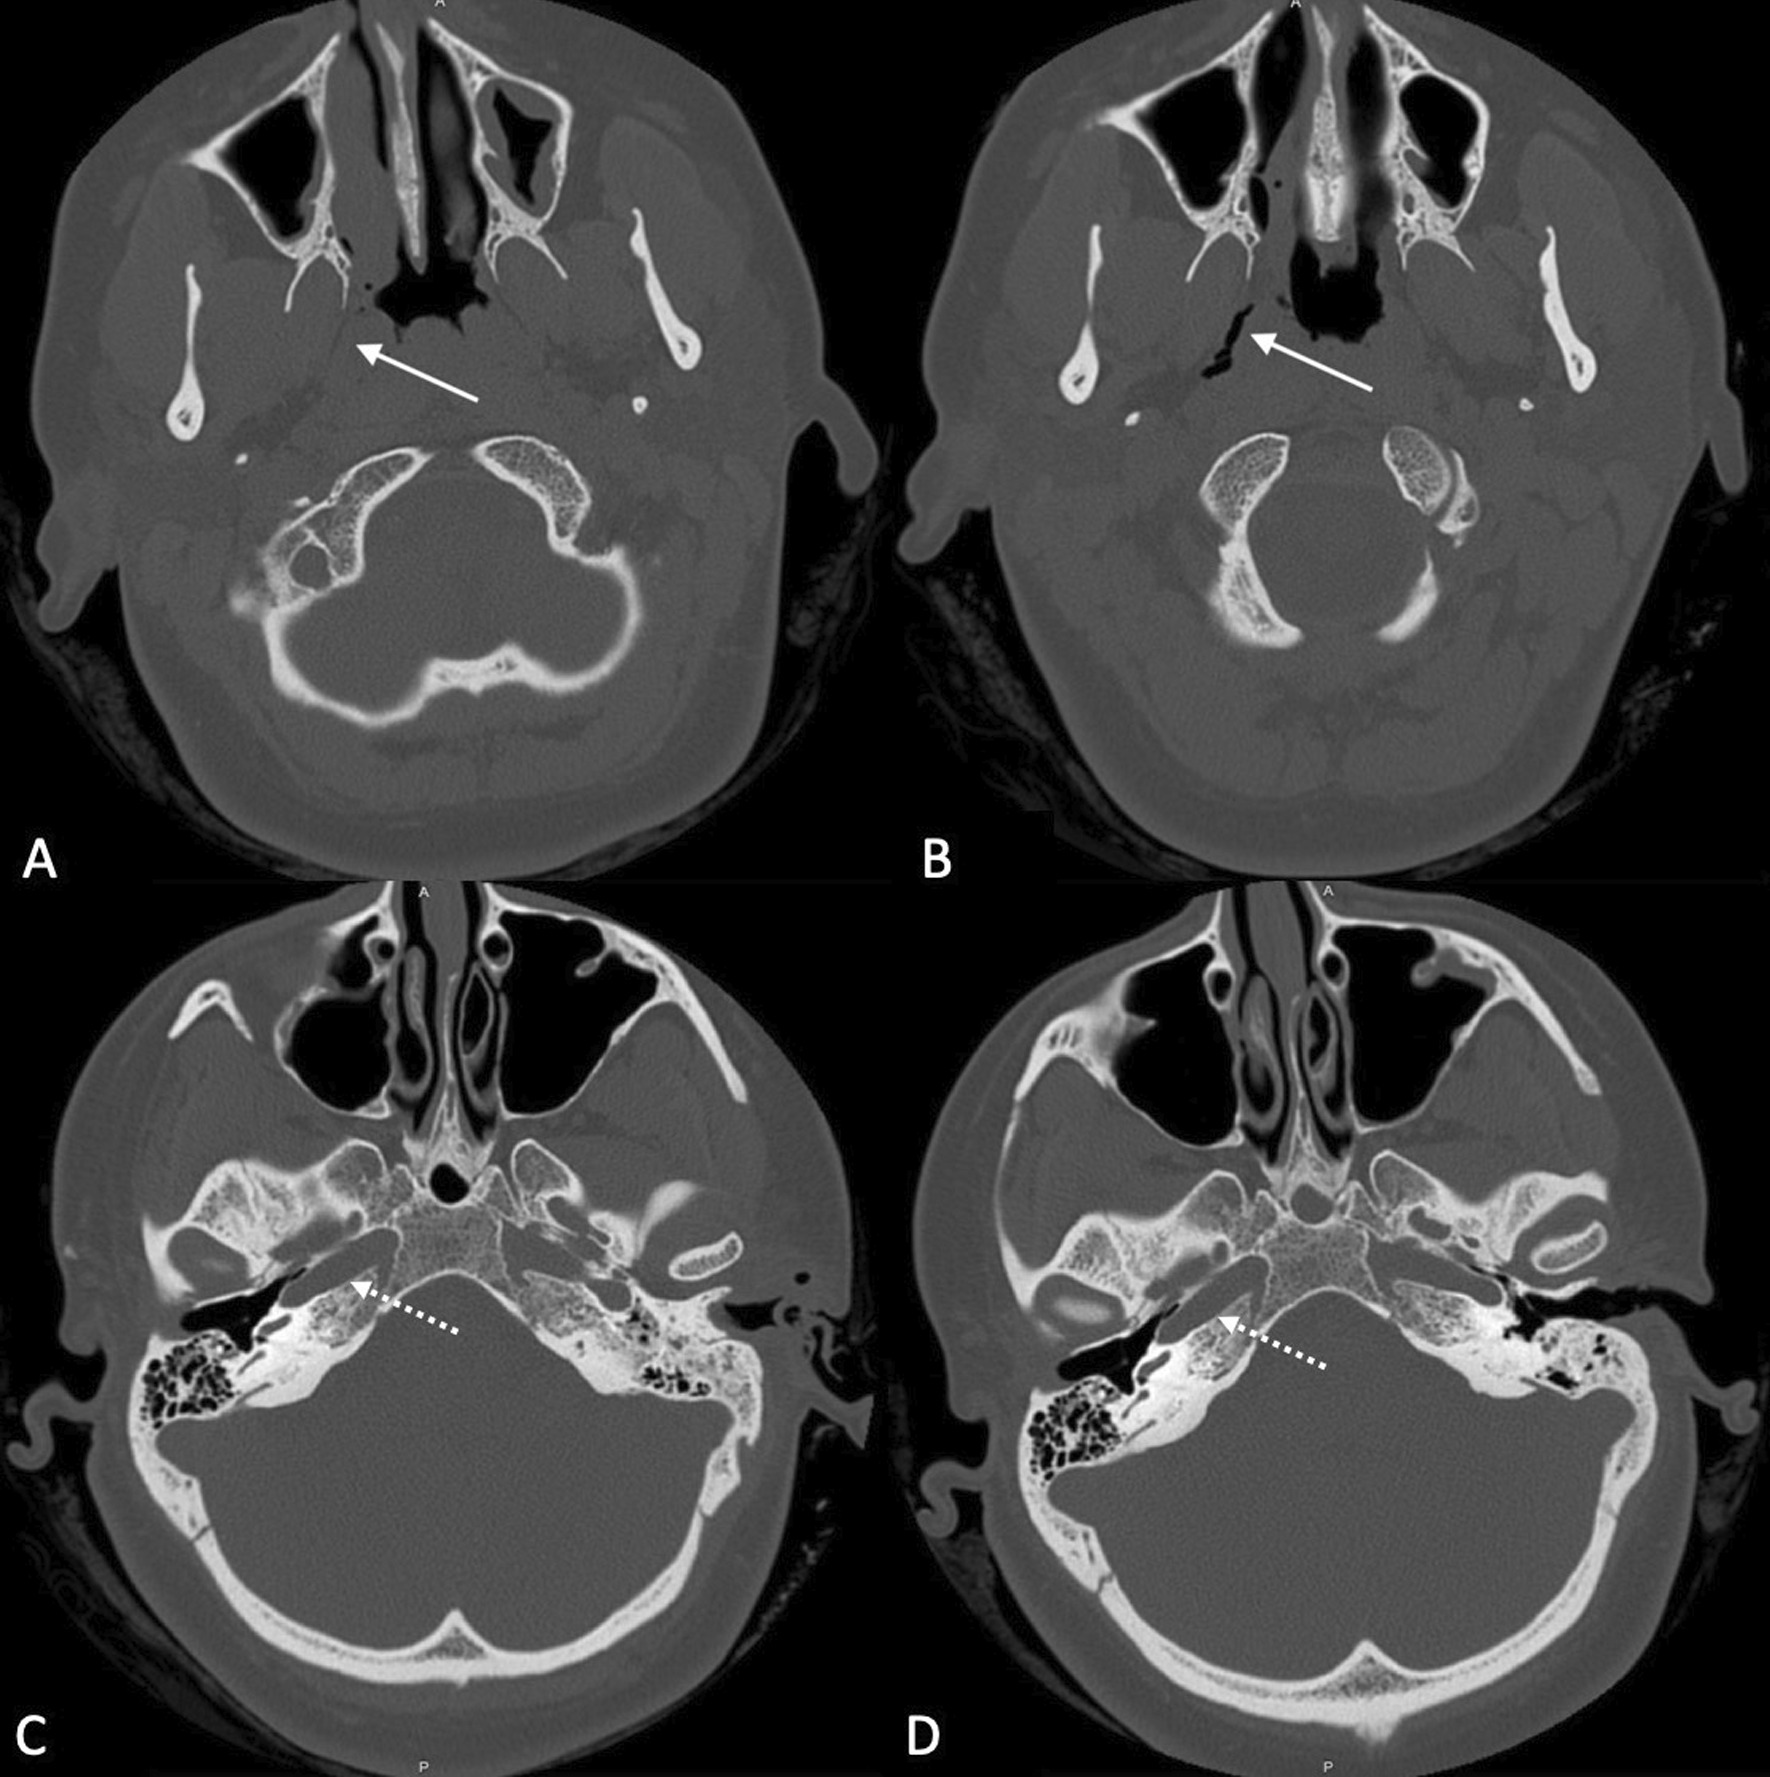

Fig. 4.

Comparison of pre- and postoperative CT (axial view). A preoperative CT, solid arrow points to the eustachian tube. B postoperative CT, solid arrow points to the dilated eustachian tube. C preoperative CT, dash arrow points to carotid canal before dilation. D postoperative CT, dash arrow points to intact carotid canal after dilation of the eustachian tube—no dehiscence can be noted